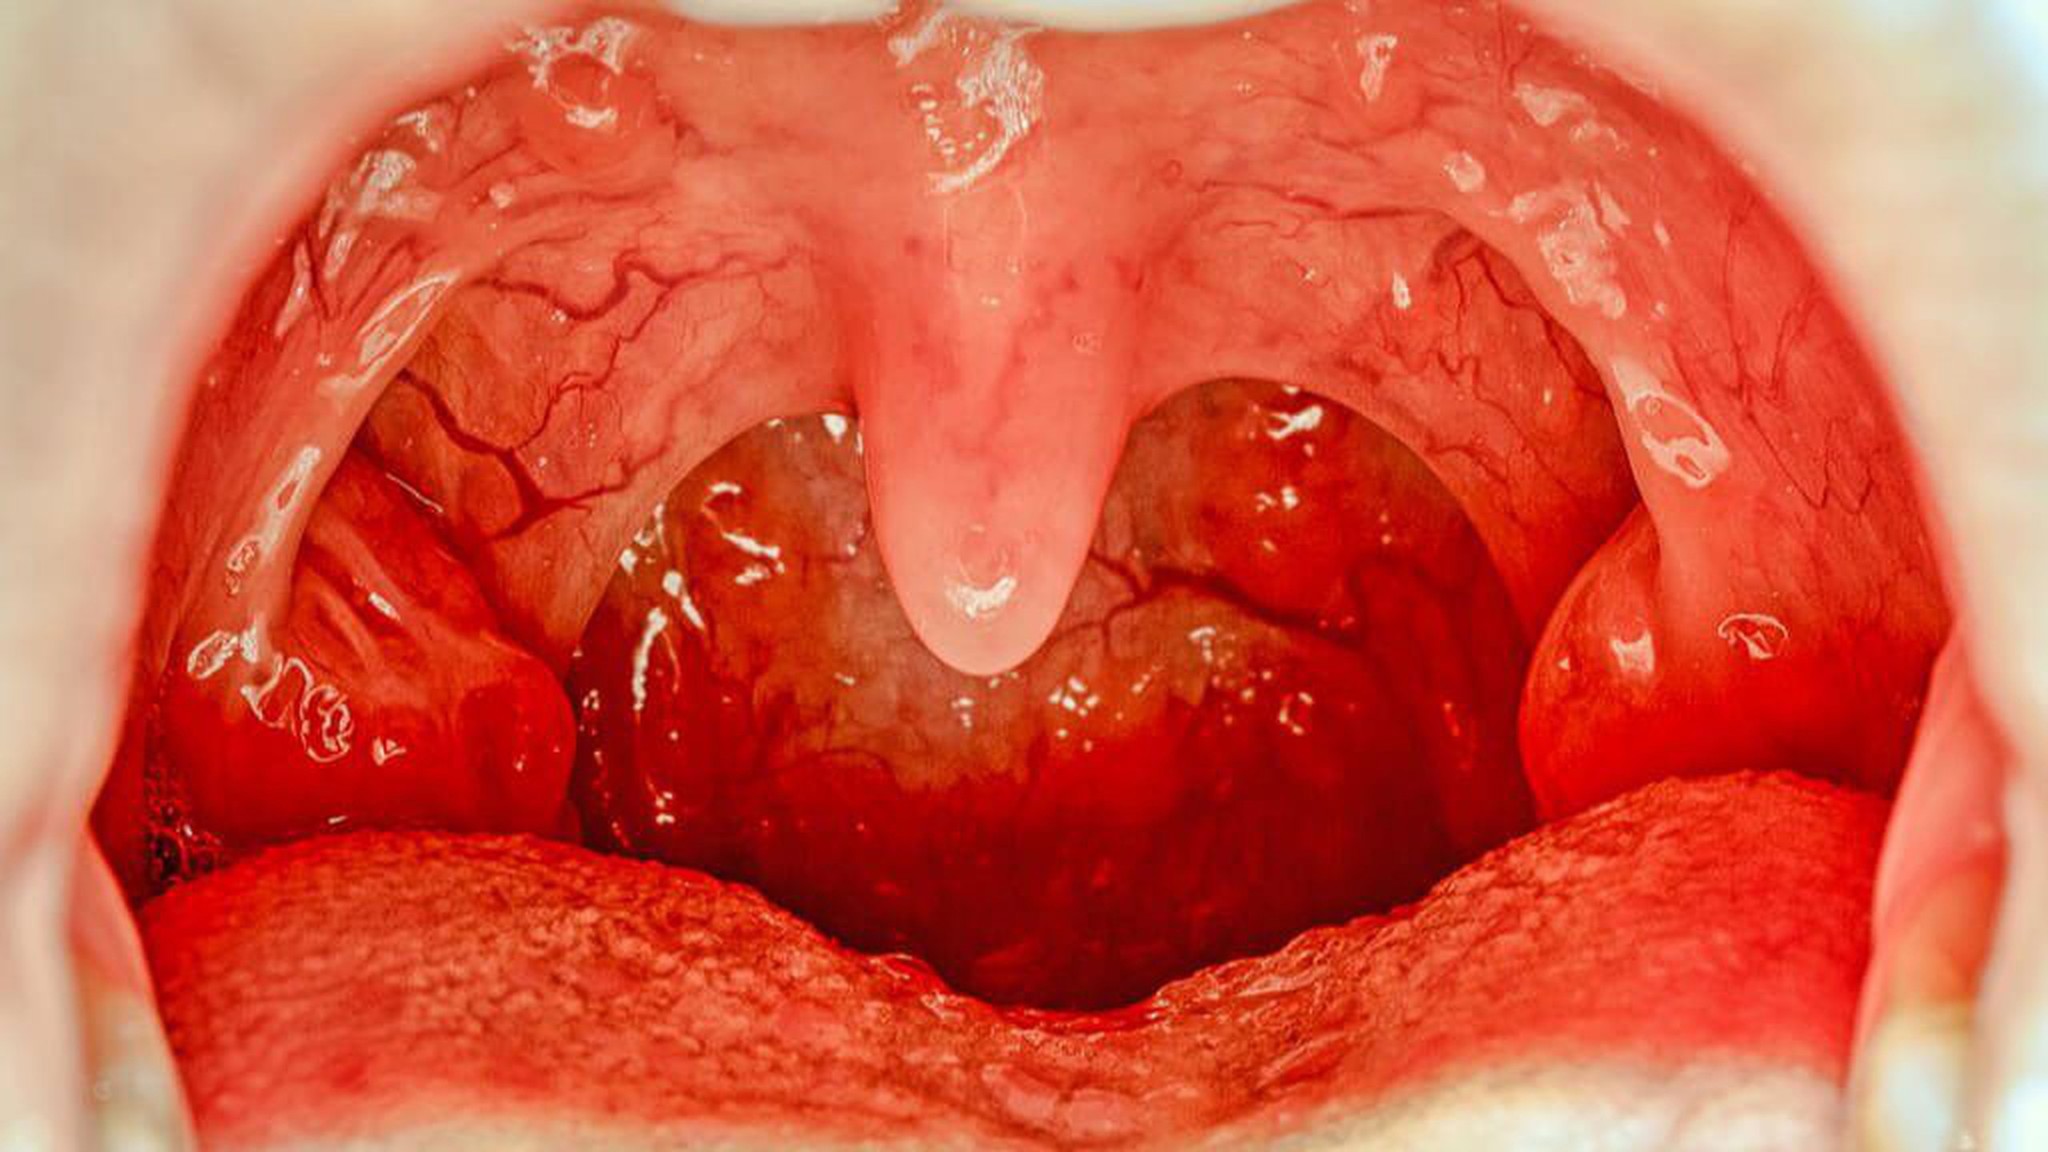

Lưỡi gà là một cấu trúc nhìn giống một mảnh thịt nhỏ treo trên vòm miệng của bạn. Lưỡi gà có tác dụng:

Viêm lưỡi gà là tình trạng viêm sưng lưỡi gà. Khi lưỡi gà bị viêm sưng lên, bạn có thể cảm thấy khó chịu và tình trạng này thường là tạm thời.

Viêm lưỡi gà là một tình trạng phổ biến. Nó thường xuất hiện khi các khu vực xung quanh miệng của bạn bị viêm, như họng, amidan hoặc vòm miệng.

- Lưỡi gà có màu đỏ, sưng và to hơn bình thường;

- Đốm trắng trên lưỡi gà hoặc cổ họng;

- Cổ họng có thể bị đau và đỏ;